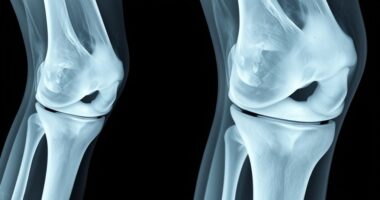

Arthrose Arthrosis or Osteoarthritis: How to Tell the Difference Arthrose und Osteoarthritis sind tatsächlich dieselbe Erkrankung, nur unterschiedliche Bezeichnungen. Sie beinhalten… Michael12/11/2025